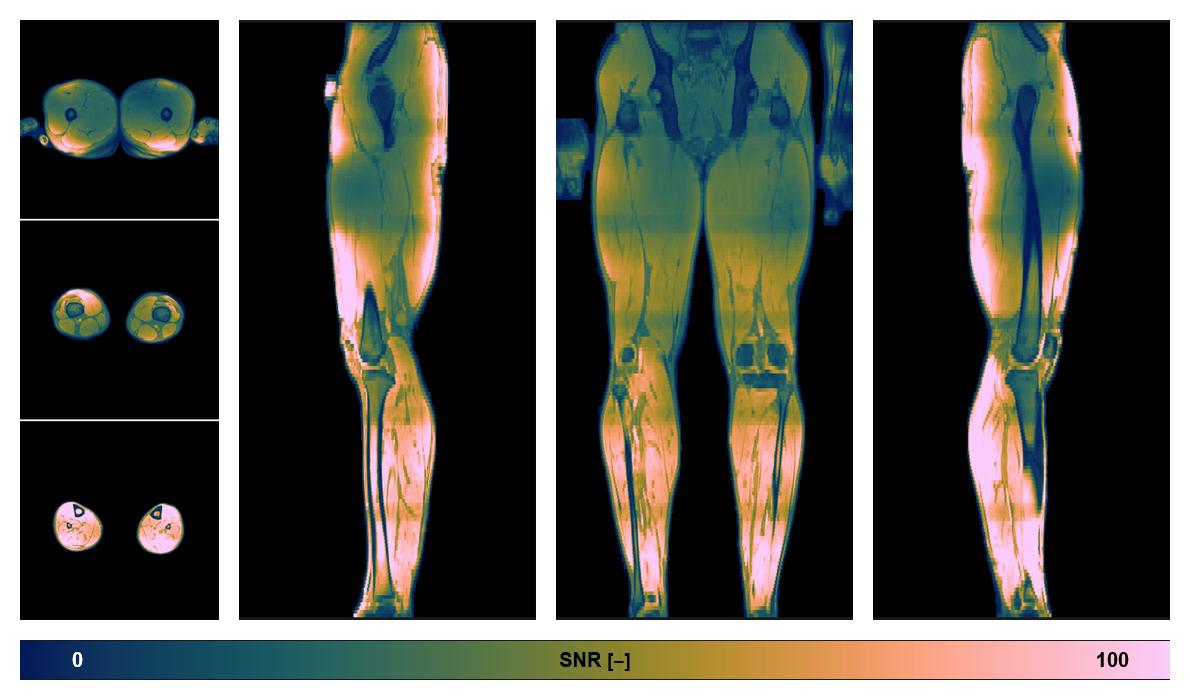

Diffusion tensor imaging

Diffusion weighted imaging with IVIM and DTI fitting to obtain muscle microstructure and muscle architecture, for information look here».

• SNR of the unweighted image

SNR distribution of the unweighted diffusion data.